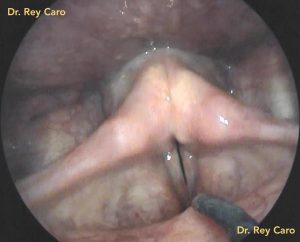

Tratamiento de la comisura anterior. Remoción de fibrina cicatrizal posterior a cirugía de la comisura anterior